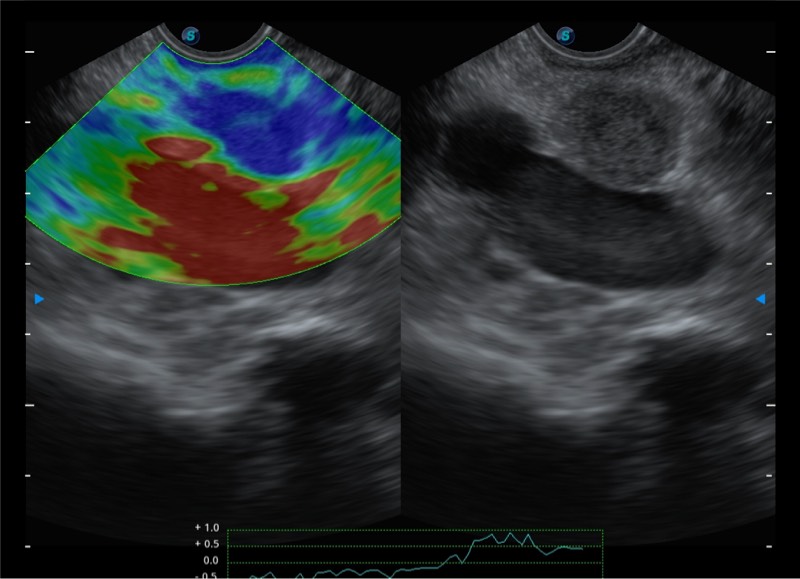

基于二十年的超声技术积累,开立提供了最新一代的独立超声主机,在提供高质量图像的同时满足多学科使用。具备常见多普勒技术并提供弹性成像、声学造影等高端影像技术。新一代传感器具有更强的抗干扰能力并减少图像伪影。

150°超声扫描角度

4-12MHZ宽频输出